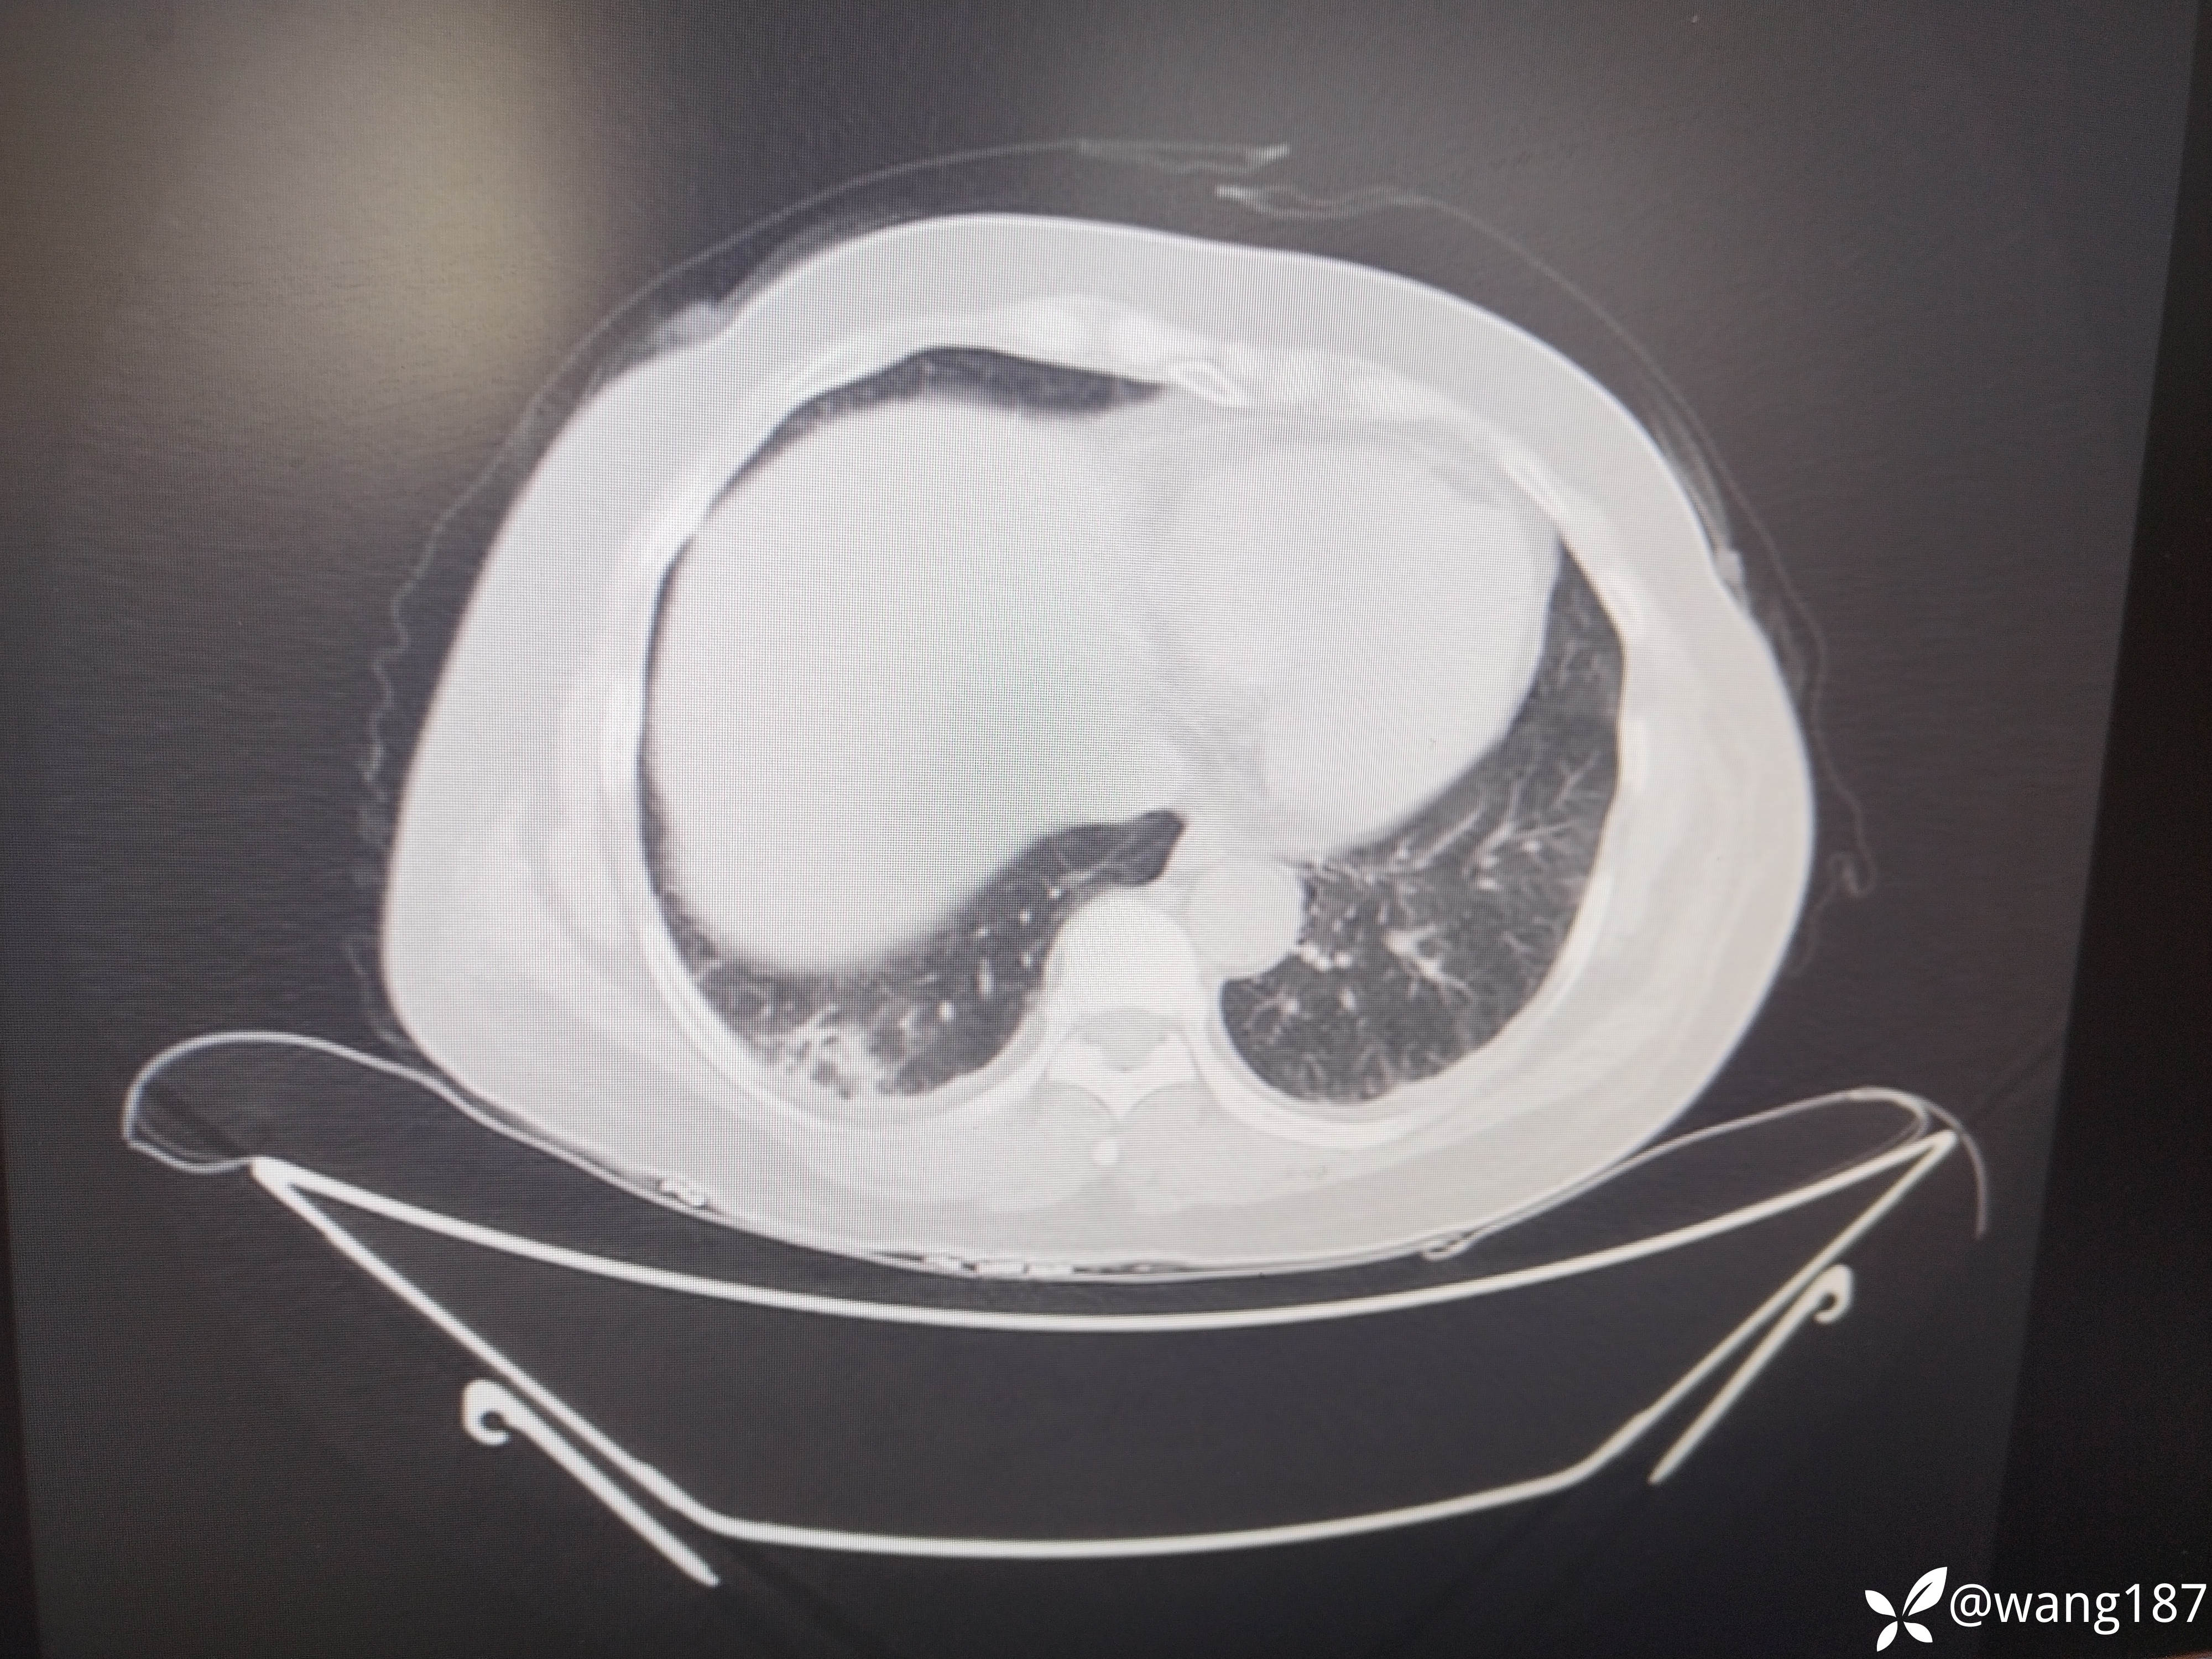

四肢肌无力伴有肌肌酸激酶升高。

患者女性,54岁,

主诉:四肢肌肉酸痛伴无力半个月,加重1天

现病史:半个月前无明显诱因出现双下肢肌肉酸痛,后出现双上肢肌肉酸痛,伴无力,伴活动受限,不能自行抬起、行走困难,伴肩背部疼痛,伴双眼睑、面部水肿,呈持续性,伴面部红斑,小便无泡沫,尿量无改变,无尿频、尿急、尿痛,无双下肢水肿,无恶心、呕吐,无心慌、胸闷,前往“当地医院”查心电图(2025-04-16):1、窦性心动过速2、T波异常 (可能是下壁心肌缺血)心肌酶谱(2025-04-16):血清肌酸激酶:8736U/L乳酸脱氢酶727U/L肌酸激酶同工酶52.18ng/mL心肌酶谱(2025-04-18)肌酸激酶:11605U/L乳酸脱氢酶620U/L;肝功(2025-04-18):丙氨酸氨基转移酶121U/L天门冬氨酸氨基转移酶429U/L谷氨酰氨基转移酶110U/L,尿常规:蛋白质+-尿潜血 2+;糖化血红蛋白(2025-04-18):8.1%;肩关节超声(2025-04-16)提示:1、肱二头肌长头腱腱鞘炎肌炎2、肩峰下-三角肌下滑囊炎,颈椎

上膜增厚。下肢肌电图未见异常,诊断为“横纹肌溶解”给予输液治疗(具体不详),症状无好转,1天前四肢肌肉酸痛伴无力症状加重,为求进一步诊治,遂来我院门诊以“1、皮肌炎2、2型糖尿病”为平诊收入我科,自发病以来,神志清,精神差,食欲差,睡眠差,大小便正常,近期体重未见明显增减。